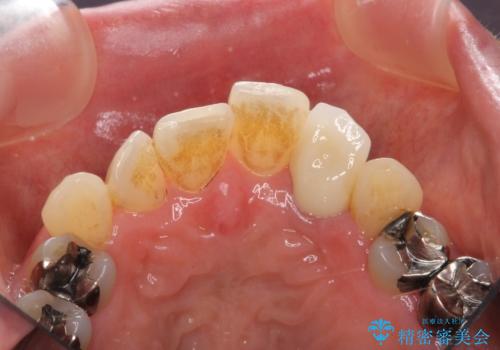

- 目立つ前歯の著しい変色の改善を求めて来院されました。

根管治療が為されたまま、クラウンの装着が行われず変色し審美障害を来している状態です。

維持を保つためのファイバーコア築盛を行い、精密なジルコニアクラウン製作を行います。